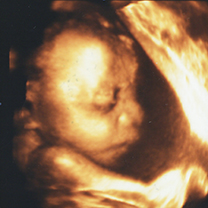

3Dエコー/4Dエコー(4D超音波)

- エコーの写真は、差し上げておりますが、動画が欲しい方は、エコー機のモニター画面のみに限り、患者様が持参されたスマホやビデオで撮影していただく事が可能です。(院内の別の場所やスタッフ、他の患者様などは、撮影しないでください)

- 当院で妊婦健診を行っている方は、13週以降、毎回3D/4Dエコーを行います。(追加料金はありません)

- 他院で妊婦健診を行っている方は、1回10分程度の検査で、料金は4300円です。

- 3D/4Dエコーに適している時期は妊娠15週~29週頃です。

- エコーは、ご主人やお子様、ご両親など家族の方と一緒にご覧になることが可能です。

*条件により赤ちゃんの顔が、見えない場合もあります。